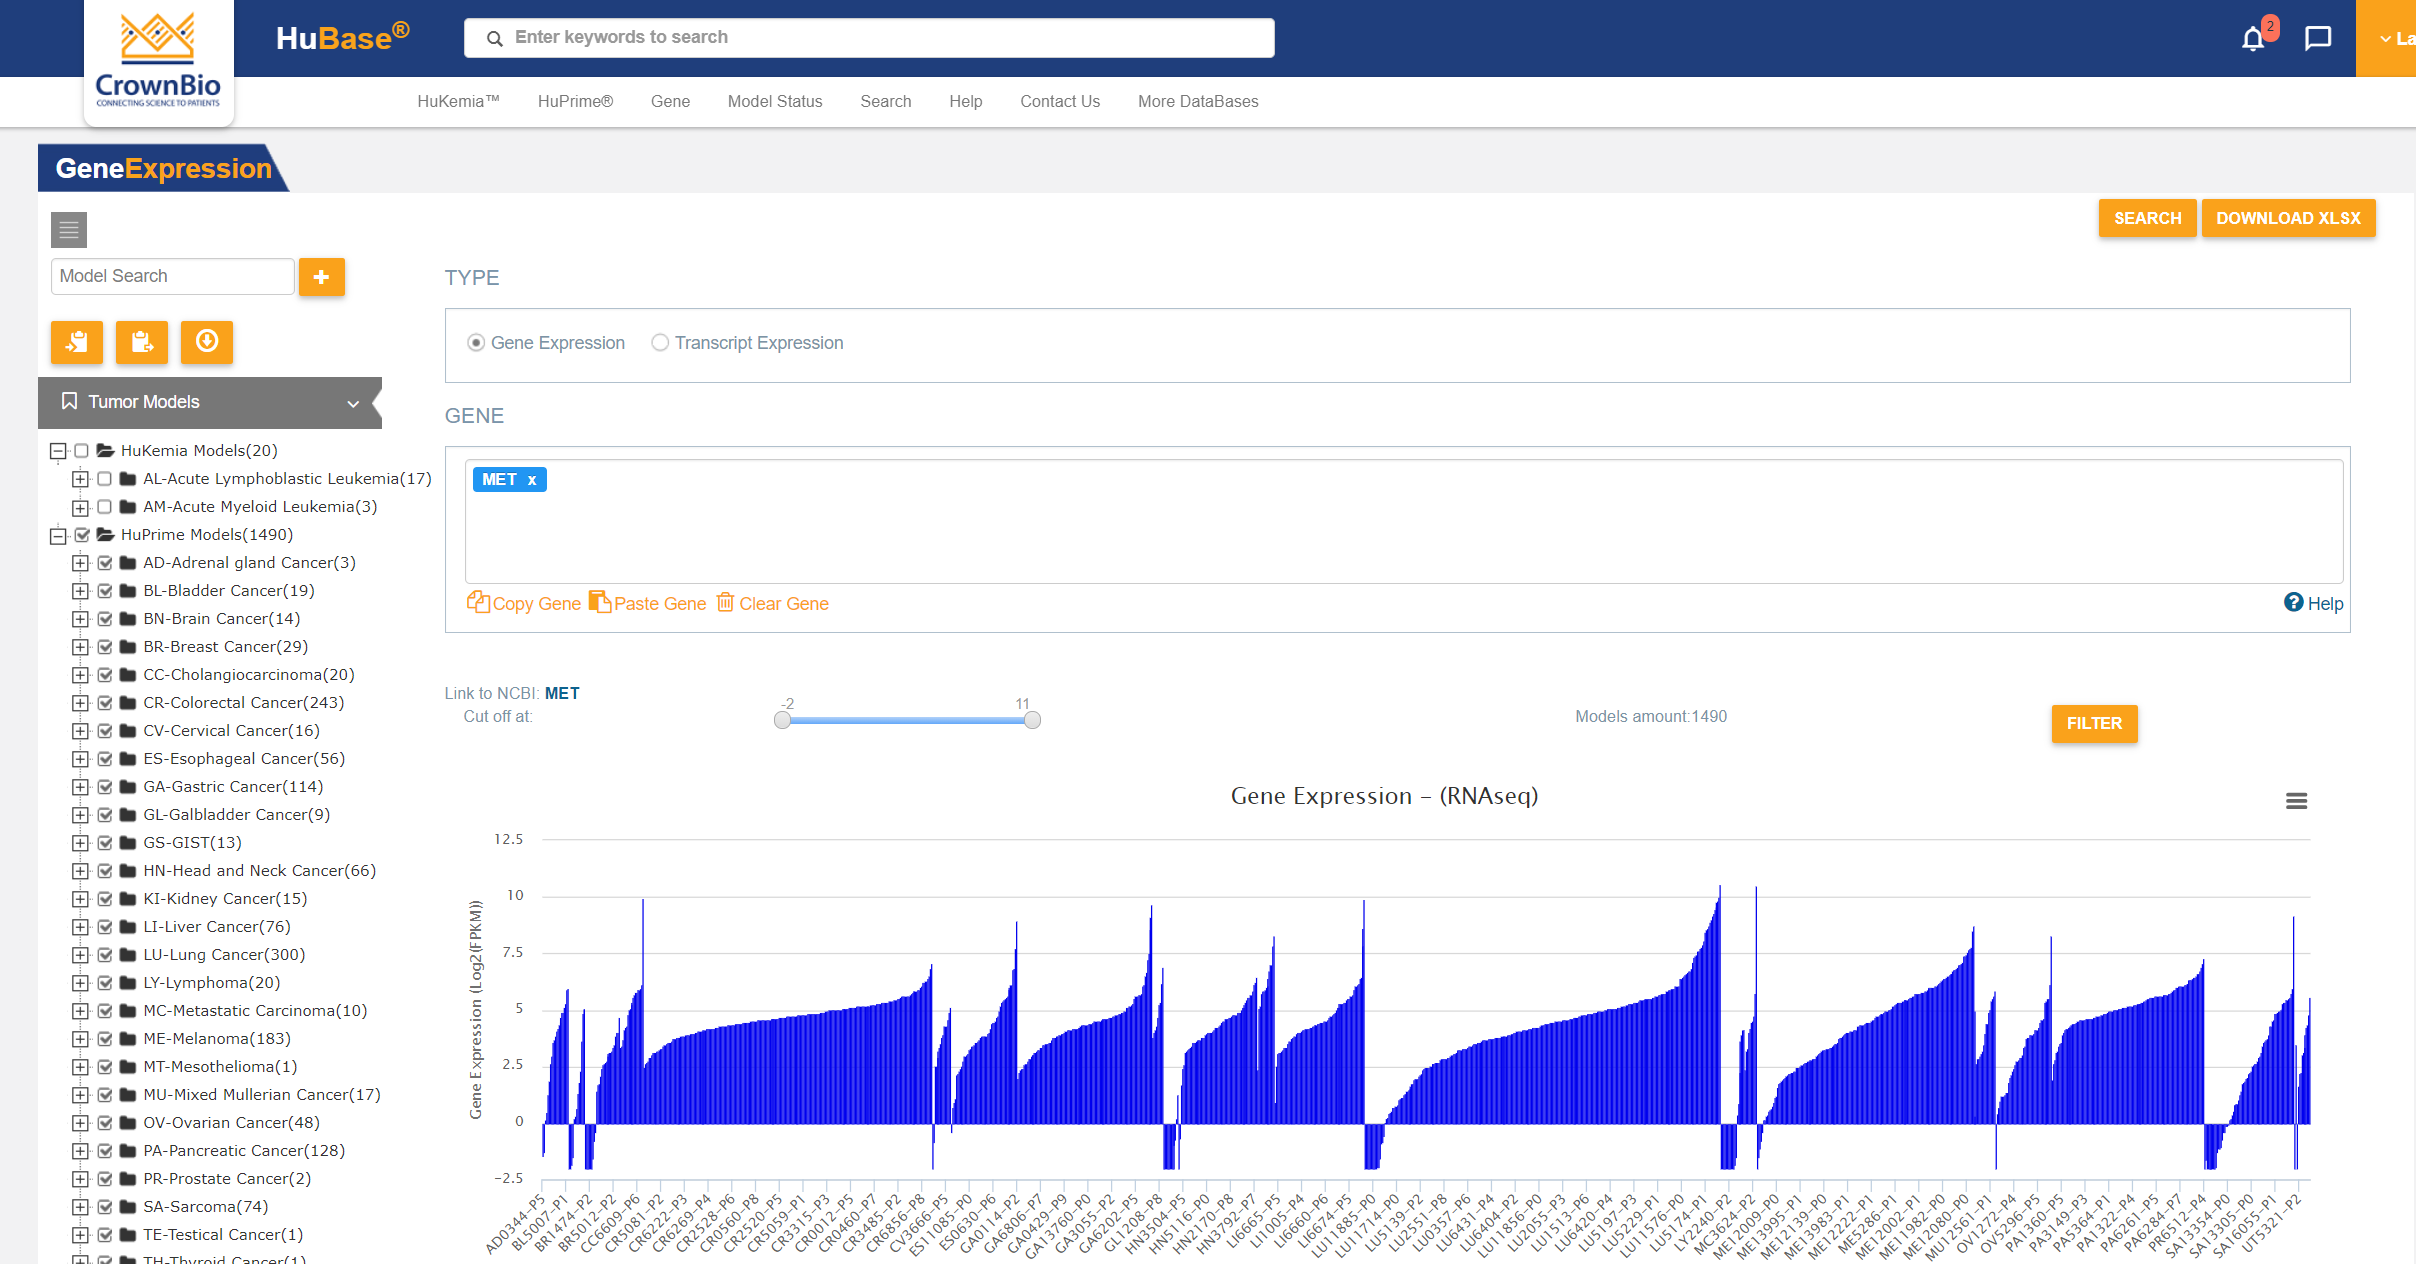

可搜索PDX模型数据库HuBase™中的大量特性鉴定数据包括:超过1,500个模型的RNAseq、超过680个模型的全外显子组测序、组织学、生长动力学以及SoC和研究性治疗数据。

具有典型白血病症状和最终死亡率的稳定模型,真实地代表了人类的情况。选择具有患者相关突变(例如: IDH2突变、FLT3-ITD(+)、BCR/ABL(+))的PDX模型来开发靶向制剂。探索大量模型特征:病理学、生长特性和对标准治疗实验制剂的反应。利用基因和基因组注释搜索符合您研究需求的模型。模型具备基因表达、基因拷贝数、突变和融合等特征。

搜索PDX基因组信息,例如:MET扩增用RNAseq基因表达数据和WES基因拷贝数数据。